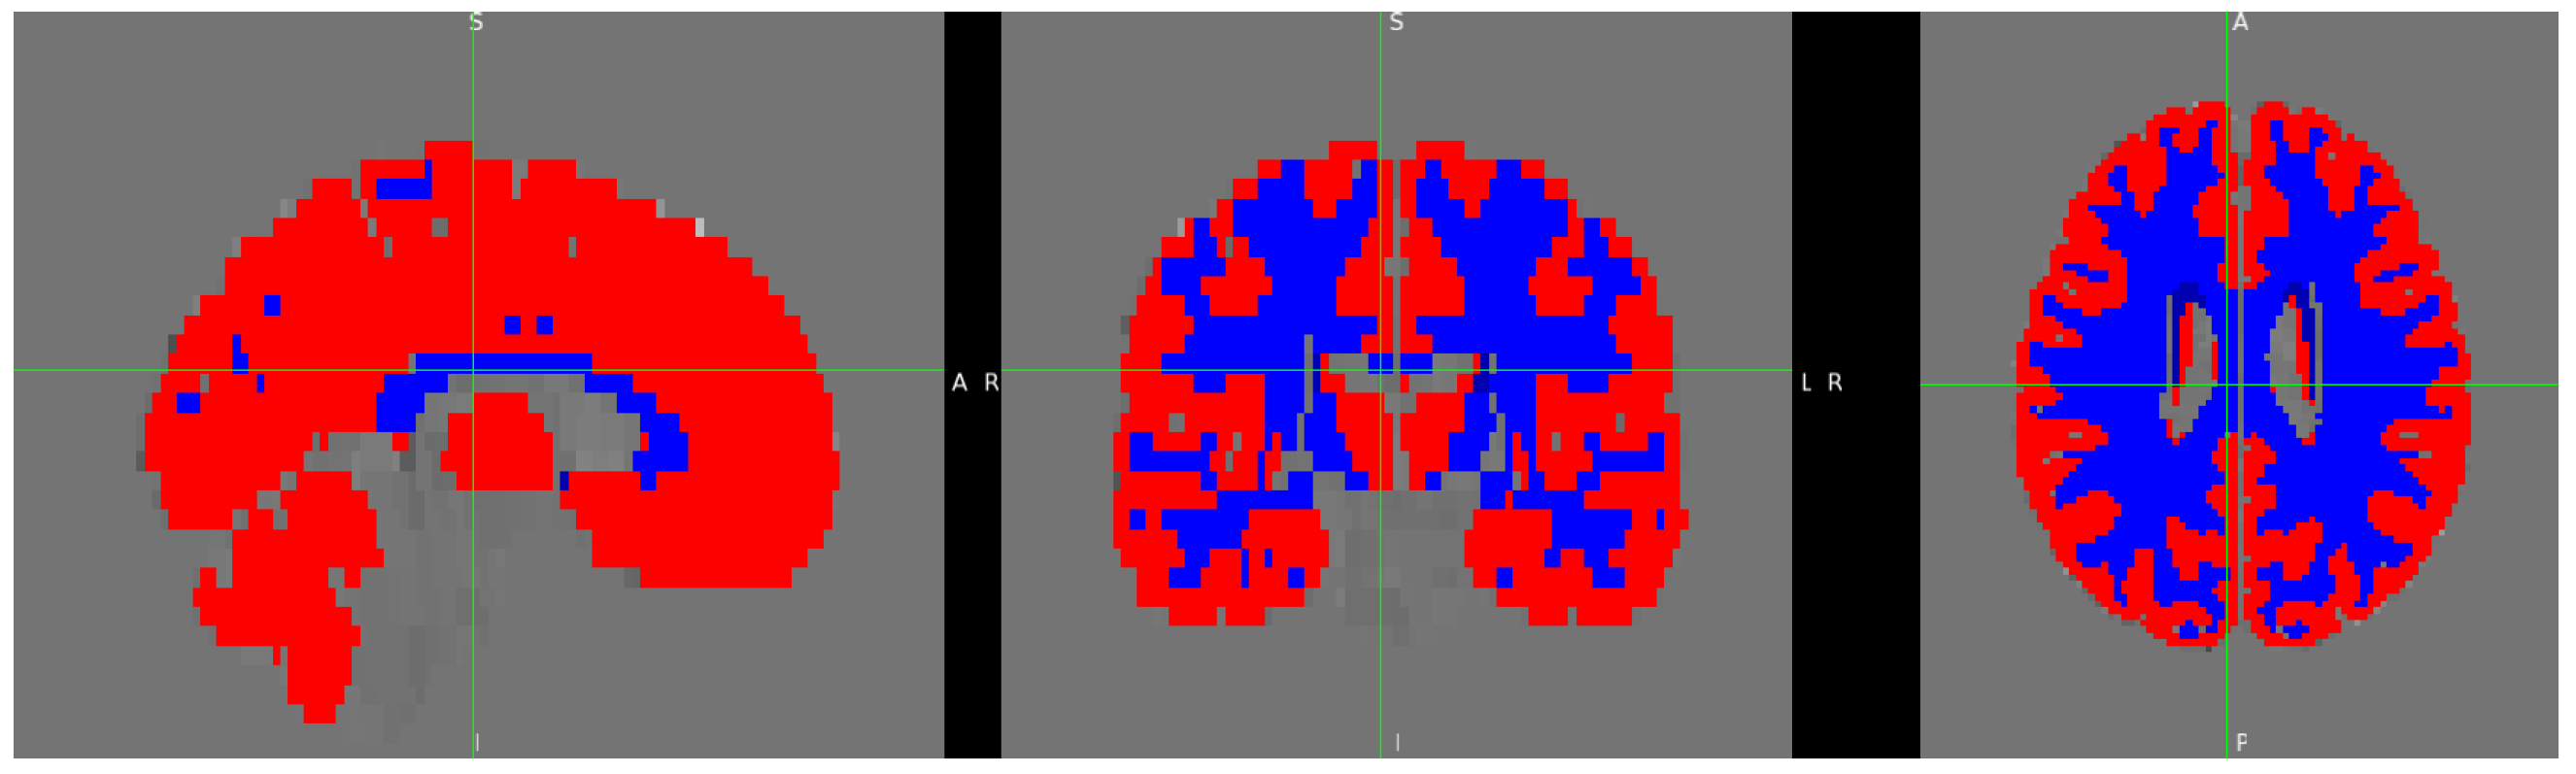

2. Materials and Methods

2.4. Procedure